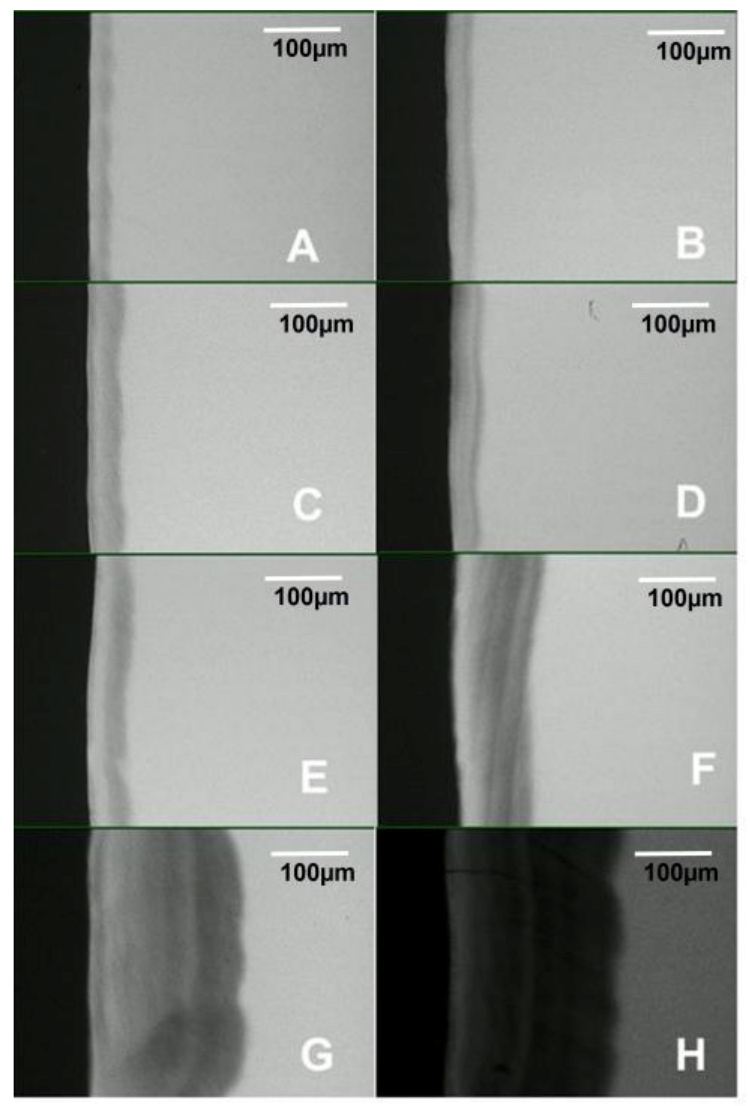

With the visual evaluation of the samples, white spot lesions (early-stage dental caries) were observed at every measurement time period in all blocks (Figure 2). Each white spot lesion (WSL) appears opaque and chalky, with a dull (matt) surface when air-dried for 5 s. It feels rough when the tip of a dental explorer is moved gently across the surface. ICDAS score 1 lesions were observed in samples exposed for 3 days (Figure 2A), while 4, 5, 6, 7, and 14 days produced ICDAS score 2 lesions (Figure 2B–F). At 21 and 28 days, the lesions were scored 3 due to observed cavitations with depth limited to the enamel (Figure 2G,H). Visually, the lesion severity increased with the increase in the length of exposure to biofilm (Figure 2).

Pearson’s correlation coefficient indicated a strong positive correlation between the biofilm growth time and lesion depth measured with PLM (R2 = 0.9946, p < 0.001) and TMR (R2 = 0.9929, p < 0.001), as shown in Table 1. Also, there was a strong positive correlation (R2 = 0.9908, p < 0.001) between the biofilm growth time and the amount of mineral loss (Table 1). Both the lesion depth evaluated by PLM (Figure 3) and TMR (Figure 4) and the mineral loss (Figure 5) increased with the increase in the length of exposure to biofilm (Table 1). In all these cases, the analyses showed a similar trend of a linear relationship. A similar trend of linear relationship and a strong positive correlation (R2 = 0.9850, p < 0.01) were observed between the lesion depth measured with PLM and that measured with TMR (Table 1). Also, at each measurement time point, there was no significant difference between the lesion depth measured with PLM and that measured with TMR (Table 1). Furthermore, there were no significant differences in lesion depth in samples harvested from day 4 through day 7. Similarly, there were no significant differences in mineral loss in samples harvested from day 4 through day 7.

Examination of the PLM and TMR images shows that the WSL has two layers: a relatively sound surface layer and a subsurface demineralization, and this is more defined at 7 days (Figure 2E) but poorly defined at other time points.

The observation that TMR and PLM lesion depth results showed a strong linear relationship with each other and with the length (time) of caries formation agrees with the reports of a previous study by Ten Bosch and Angmar-Mansson [30]. These established linear relationships would allow estimating the time needed to obtain specifically sized lesions depending on the requirements of any proposed study. PLM images of the lesions after 21 and 28 days of caries formation showed defects such as fractures and cracks below to the outer enamel surface (Figure 2G,H), which could be caused by the excessive exposure time causing extreme demineralization and weakening of the enamel structure. Also, the profile of mineral loss (Figure 5) of these last two assessment time periods showed an irregular lower edge of the lesion body in comparison with lesions from the other time periods. These two conditions could provoke the overestimation of the mineral loss (in these conditions the software translates the internal enamel defects as highly demineralized areas), suggesting that the limit to produce caries lesions with this model would be 14 days, but 7 days for lesions targeted for remineralization study.

Figure 2. Visual appearance of white spot lesions (early-stage dental caries) produced in the artificial mouth model after 3 (A), 4 (B), 5 (C), 6 (D), 7 (E), 14 (F), 21 (G), and 28 (H) days of exposure to biofilm growth. Magnification 120×.